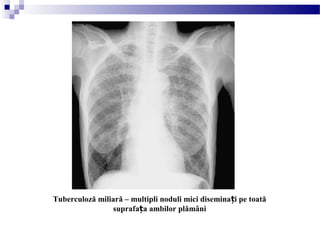

Tuberculoză miliară – multipli noduli mici disemina i pe toatăț

suprafa a ambilor plămâniț